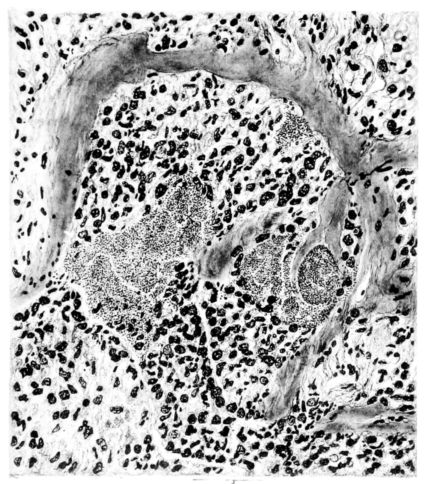

FIG. III. AUTOPSY NO. 90. DRAWING FROM A LESION OF THE TRACHEA (SOMEWHAT OLDER THAN THAT ILLUSTRATED IN FIGURE II). THE MUCOSA IS ENTIRELY LACKING. CONGESTION AND EDEMA ARE THE STRIKING FEATURES IN THE SUBMUCOSA. THE NECROTIZING PROCESS HAS EXTENDED INTO THE MUCUS GLANDS. THIS IS SHOWN IN THE LOWER PICTURE.

The changes are less marked, perhaps, in the trachea than in its finer ramifications. The mucosa is constantly more or less destroyed and large areas, usually focal, are entirely devoid of their epithelial covering. This is replaced by a sparse exudate, composed largely of red blood cells, mucus, a small amount of fibrin, and nuclear fragments (Fig. II). It may dip into the submucosa for a short distance, but usually these indentures are associated with the ducts of the mucous glands into which the inflammatory reaction extends. A more striking feature than the exudate, however, is the edema and the congestion of the submucosa. The loose areolar tissue of the submucosa is spread widely apart, and throughout it distended blood vessels are very conspicuous. Occasionally such a vessel is broken and actual hemorrhage appears in the submucosa. Occasionally, too, the inflammation extends down the duct to the mucous gland itself, and here, also, aplastic inflammatory reaction is evident, inasmuch as the acini now stain intensely red with the cells undifferentiated from each other and specked here and there by broken remains of the dead nuclei (Fig. III). After the disease has continued for a short period, even at the end of five or six days, some regeneration of the epithelial lining may be seen (3) (Fig. IV). But despite this, the acute picture persists, and there goes on, side by side, an attempted repair characterized by epithelial regeneration and the same evidence of acute change. Since the lesion is essentially a superficial one, scars or contractures of any extent are not encountered in the trachea, even in examples of the disease that have ended fatally only after many weeks.[4]